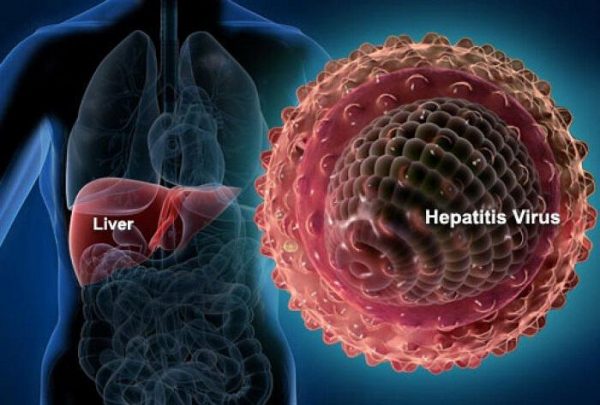

- Η ιογενής ηπατίτιδα εξακολουθεί να μαστίζει εκατοντάδες εκατομμύρια ανθρώπους στον πλανήτη και αποτελεί τεράστιο πρόβλημα δημόσιας υγείας.

- Στην Ελλάδα, υπολογίζεται ότι 200.000 άνθρωποι είναι φορείς της ηπατίτιδας Β και 80.000 άτομα της ηπατίτιδας C. Ιδιαίτερο γνώρισμα της χρόνιας ηπατίτιδας είναι ο ασυμπτωματικός χαρακτήρας της, με αποτέλεσμα πολλά από τα άτομα που έχουν μολυνθεί να μην το γνωρίζουν.